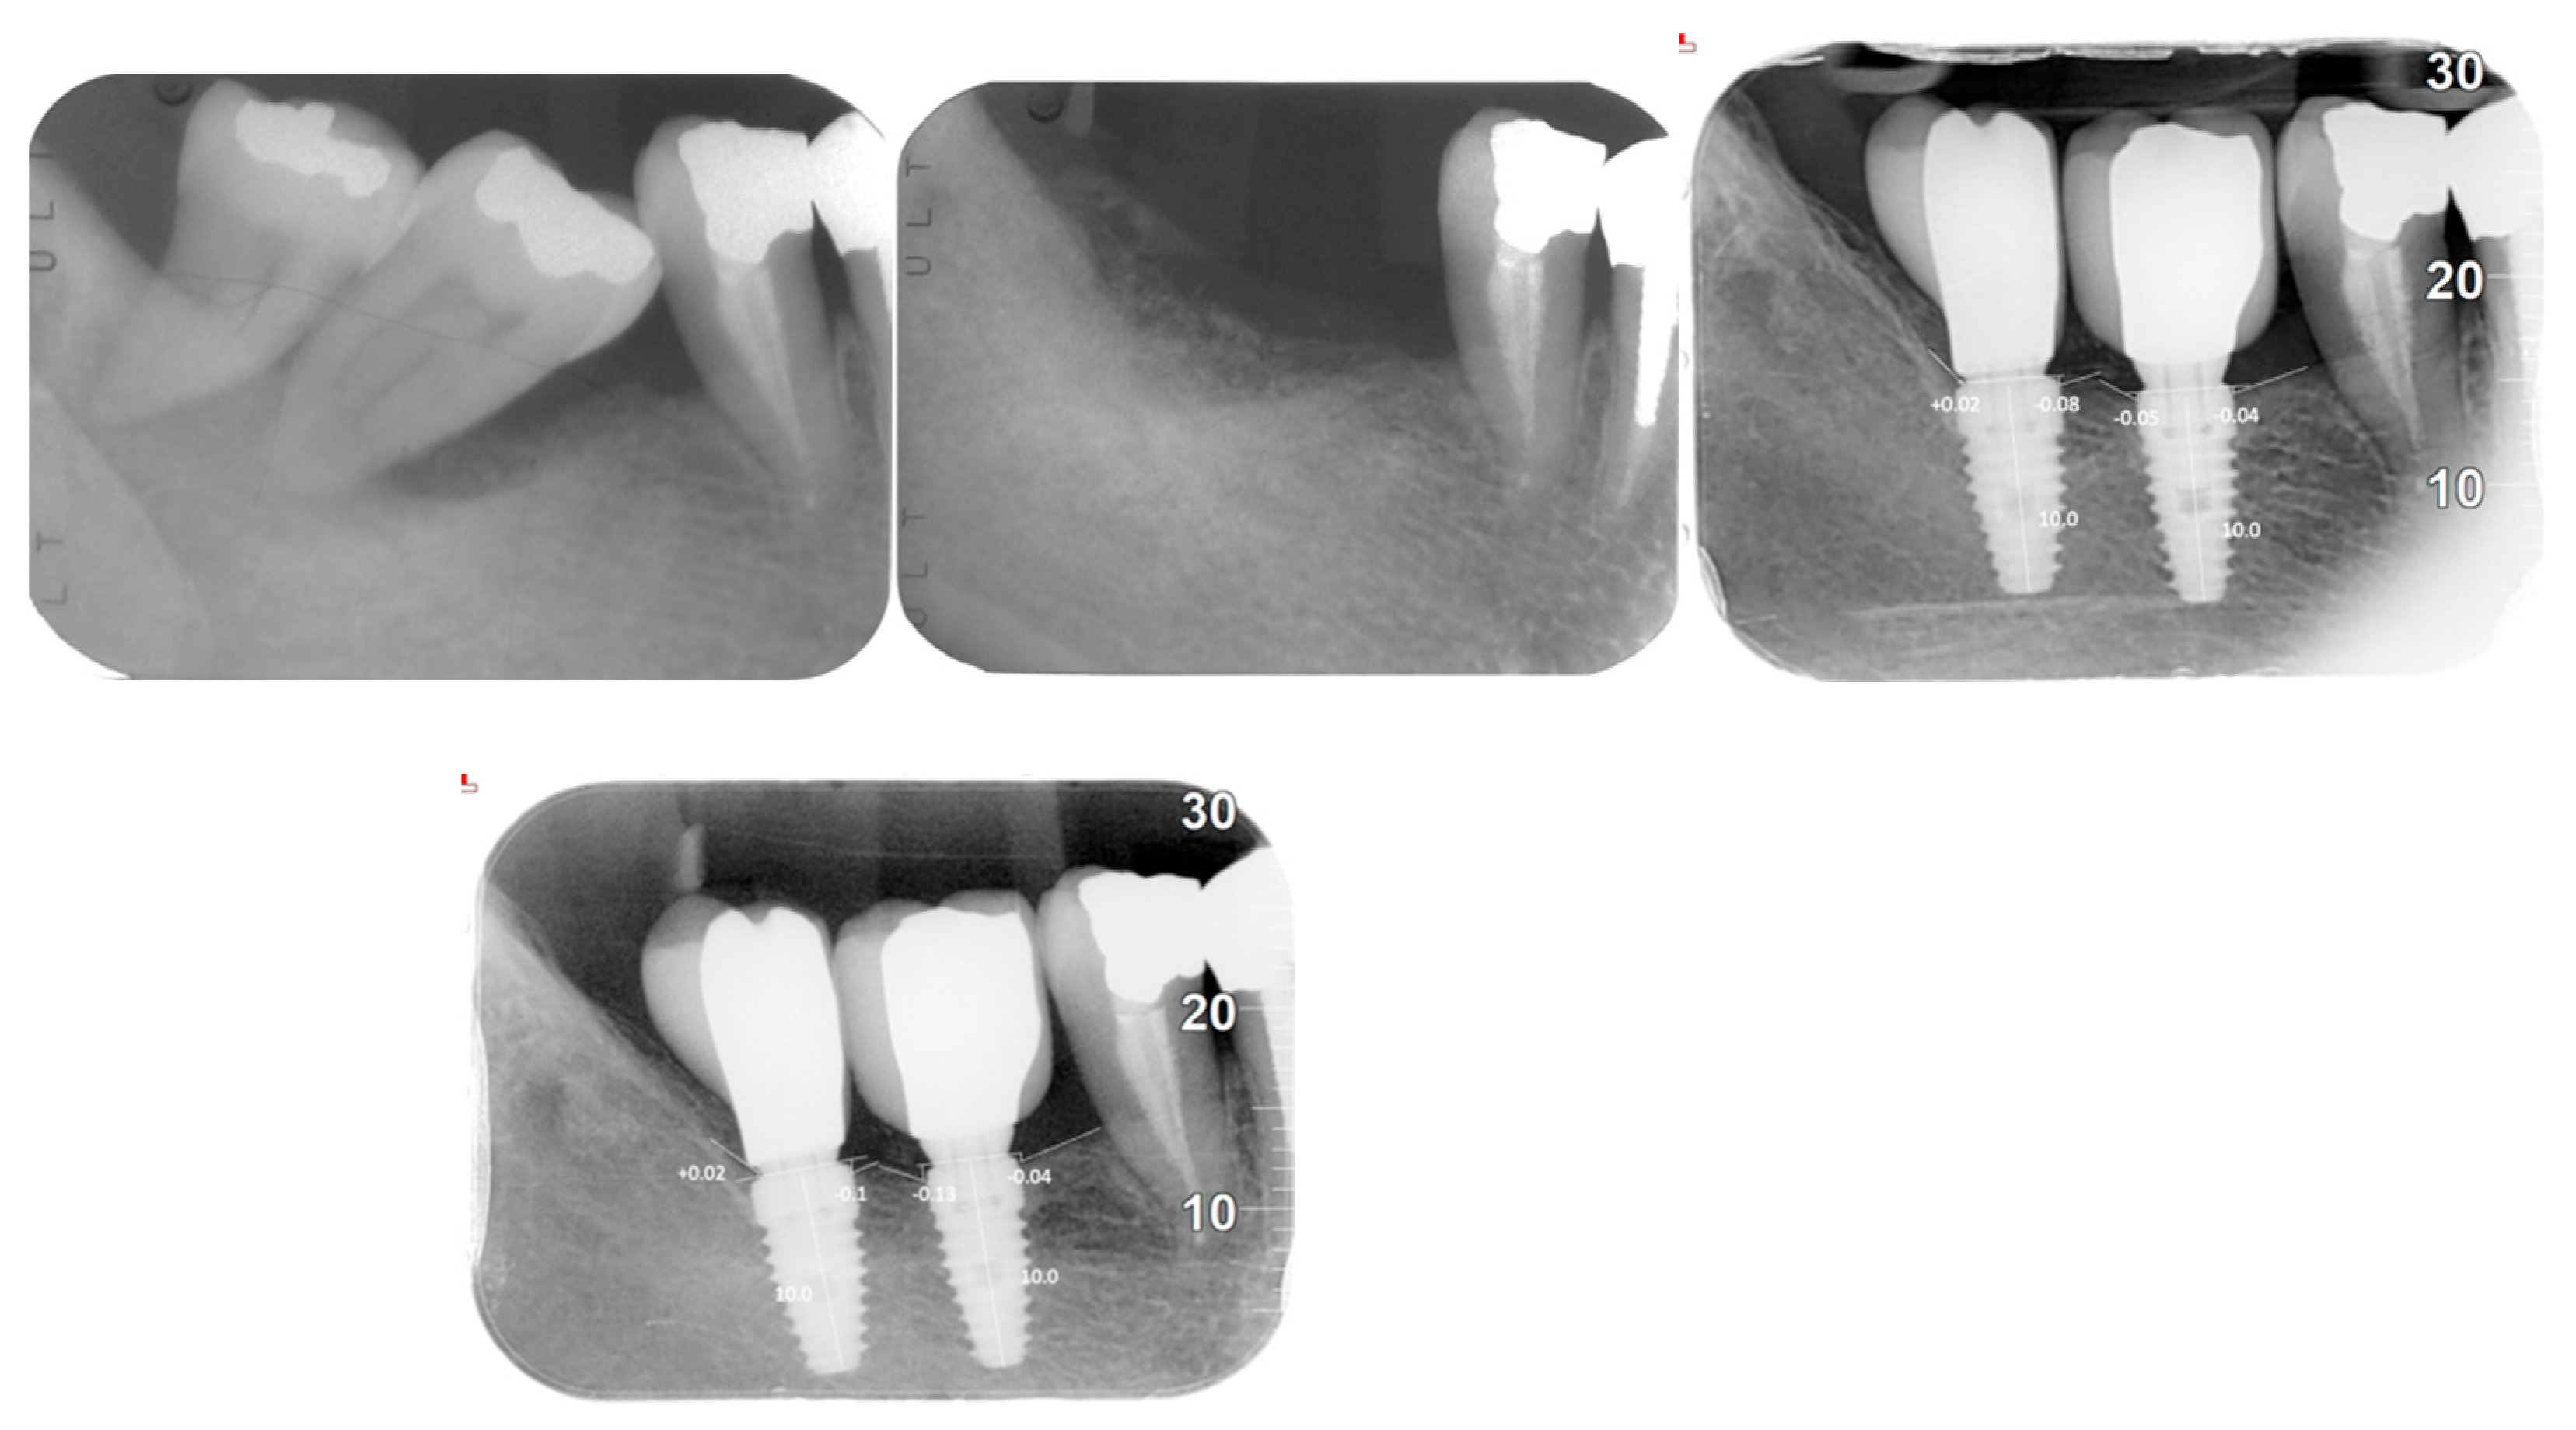

| Evaluation Methods | Orthopantomograms (OPG), cone beam computed tomography (CBCT), intraoral radiographs, clinical examinations |

| Peri-implant Bone Loss | Mean: 0.1208 mm (±0.1307) |

| Mesial Bone Loss | 0.14302 mm (±0.0107) |

| Distal Bone Loss | 0.09934 mm (±0.0143) |

| AVERAGE BONE LOSS | 0.1208 + −0.1307 |

| Mesial bone loss | 0.14302 + −0.0107 |

| Distal bone loss | 0.09934 + −0.0143 |